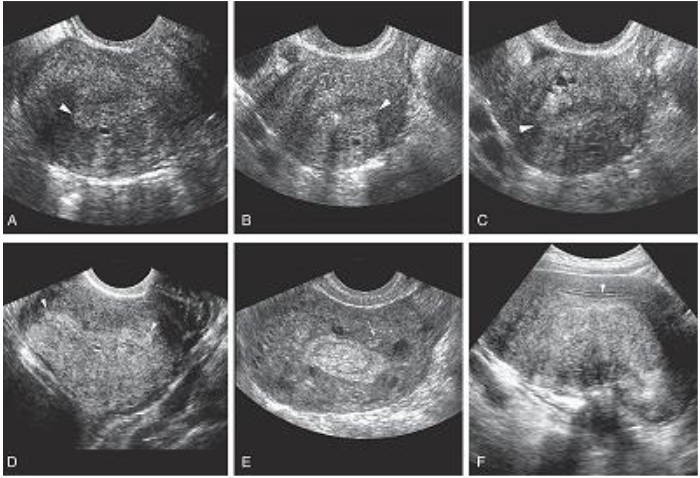

Sonographically, diagnosis may be difficult.

Most common presentation of extensive adenomyosis is:

➢ Diffuse uterine enlargement

➢ Thickening of posterior myometrium

➢ Indistinct border between endometrium and myometrium (involved area being slightly more

anechoic than normal myometrium)

Has been described as Swiss cheese or honeycomb pattern

Calcifications resulting from prior instrumentation are seen along inner myometrium and cervix.

Doppler studies have also proven helpful in differentiating uterine pathology, as color flow studies of

uterine masses show that myomas and sarcomas typically demonstrate a feeding artery, but

adenomyosis rarely demonstrates feeding arteries.

Adenomyosis is not always reliably diagnosed by ultrasonography, and

caution is advised because these findings are similar in appearance to

uterine myomas, muscular hypertrophy, myometrial contractions,

endometritis, endometrial carcinoma, and the presence of increased

endometrial secretions.

The presence of myomas has been shown to limit the ability to diagnose

the severity of adenomyosis.

Although not reliably diagnosed by ultrasonography, adenomyosis is well

characterized by MRI, which currently is thought by many to be the

best technique for the presurgical diagnosis of adenomyosis.

Adenomyosis